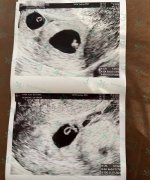

泰国试管婴儿双胎宝贝胎心棒棒的~

患者回澳洲了,根据之前医生写给的方案日期去做检查,今天双胎宝贝已经6周多了,因为发育的比较快今天就已经看到胎心搏动啦。

患者发到群里我就发给库医生看看双胎宝贝现在长得怎么样了,库医生看了回复,给两个宝宝点赞,为患者高兴,期待着出生后发照片过来分享给我们看。